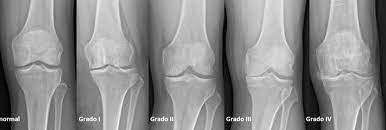

Terapia de ejercicio de dosis alta versus dosis baja para la osteoartritis de rodilla

Los resultados de este ensayo multicéntrico controlado aleatoriono respaldan la superioridad del ejercicio en dosis altas sobre el ejercicio en dosis bajas para la mayoría de los resultados. Sin embargo, se encontraron pequeños beneficios con altas dosis de ejercicio para la función de la rodilla en deportes y recreación y para la calidad de vida. Ann Intern Med, 24 de enero de 2023